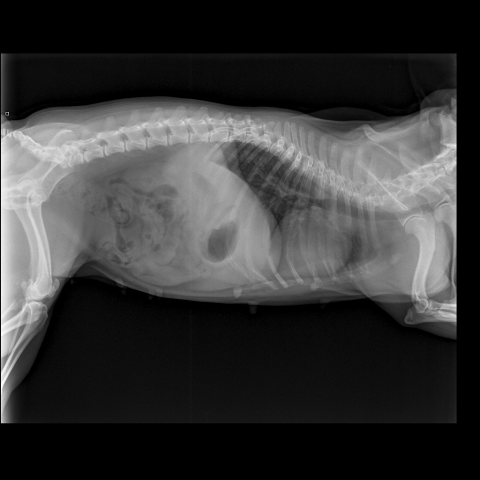

Французский бульдог,6 лет.Стала плохо ходить,что- то с позвоночником.Врачи не могут поставить диагноз.Есть снимки.Помогите!

Снимки хорошие, качественные, но совершенно не информативные. На этих пленках патология не определяется. Но здесь нет снимка, который нужен обязательно - поясничный отдел позвоночника в прямой проекции (такой, как 3-й, но только не шея, а поясница).

Нет,наоборот.Собака сначала стала немного наклонять голову вправо.Когда были на консультации у окулиста,то он обратил внимание на это ,сказал,что есть какие-то изменения в области шеи.Я отсутствовала дома 2 недели.Приехала,собаку вообще не узнала.Крен головы вправо стал еще сильнее,передние ноги как-то ослабли.Она идет,может споткнуться,упасть.Сходили,сделали рентген.снимок.Поставили диагноз:атланто-аксиальная нестабильность шейного отдела,спондилоартроз. Проколола 5 дней:актовегин,папаверин,комбилипн,мидокалм,дексаметазон. Пока делала уколы и еще дней 5 после этого собаке стало легче,а потом опять вернулись к тому, что было.На консультации врач сказал,что дальше просто колоть преднизалон. Я уехала к другому врачу,тот сделал снимки,которые я Вам отослала.Сказал, что диагноз не подтверждает,на пальцах показал, что со спинным мозгом все нормально.С помощью какой-то процедуры (бумаги на работе)обнаружил перфорацию барабанной перепонки.Выписал лечение:цефтриаксон,циклоферон,цебролизин(колола 2 дня,стало хуже),комбилипен.В уши-изотик.Сказал,что может быть у собаки был инсульт.Собаке от лечения хуже.Вот такие дела.